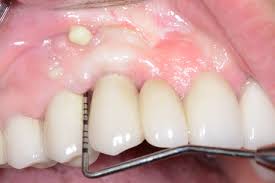

perio1

Diente y encias sanos